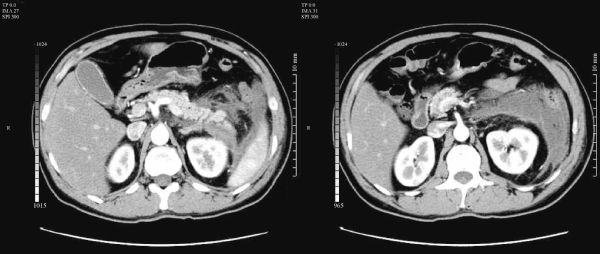

Xi Feng, Madhava Pai, Malkhaz Mizandari, Tinatin Chikovani, Duncan Spalding, Long Jiao, Nagy Habib

Hepatocellular carcinoma (HCC) is the fifth most common neoplasm in the world, closely correlated with viral hepatitis and liver cirrhosis. The vast majority of HCC patients present at a late stage and are unsuitable for surgery due to limited liver functional reserve. Tumors can involve major vessels or hilar structures, necessitating major liver resection and/or rendering liver resection unfeasible. A series of new technologies have been developed to optimise HCC management. Stem cell therapy improves impaired liver functional reserve prior to liver resection. Intravascular radiofrequency ablation recanalises the portal vein invaded by tumour thrombus and endobiliary radiofrequency ablation restores and extends biliary patency of the bile duct invaded by malignancy. Laparoscopic radiofrequency assisted liver resection minimizes blood loss and avoids liver warm ischemia, while increasing parenchymal sparing. These benefits combined maximize the safety of liver resection.